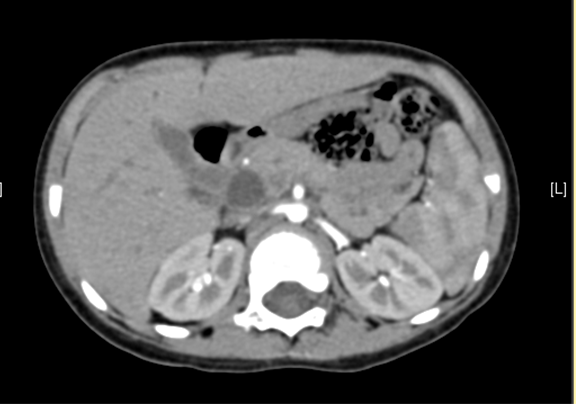

上腹部CT 动态增强:1. 肝内部分胆管-肝门部胆管-胆总管扩张,符合先天性胆管扩张症2. 胆总管下段腔内结节状略高密度影,伪影?结石?3. 胆囊壁略厚,提示胆囊炎可能。

术前CT检查:

动脉期

静脉期

平衡期